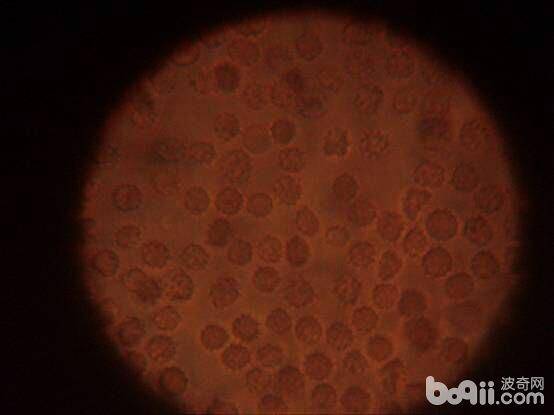

1.3 镜检

采血样滴生理盐水10倍稀释,混匀,加盖玻片,放在400-600倍显微镜下观察,发现红细胞表面及血浆中有游动的附红细胞体。

图2 镜检结果

3.1 本病多发生于夏秋季节,多见于7-9月份。本病可发生在全年龄段的犬种。本病初期病犬持续低烧、稽留热,而个别、四肢内侧、四肢肢端处出现紫癜。病程过长的会出现肢端坏死。后期出现口唇黏膜黄染,皮肤出现黄染,尿液呈茶褐色。取病犬血样滴一滴生理盐水10倍稀释,混匀,加盖玻片,放在400-600倍显微镜下观察,可发现红细胞表面及血浆中有游动的各型虫体(晚期病犬无此症状),红细胞呈星型或不规则的多边形,血涂片用姬姆萨染色,放在油镜暗视野下,可见大部分红细胞边缘变形。